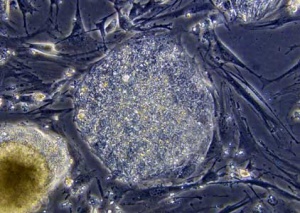

За първи път в историята на медицината бяха излолирани и отгледани стволови клетки на дебелото черво. Учените от Института по изследвания в биомедицината успешно отгледаха клетки на дебело черво в петрида. Това е голяма стъпка в регенеративната медицина, категорични са учените.

Стволовите клетки на дебелото черво имат за цел да регенерират вътрешната му част през целия живот на човека. Едва наскоро обаче те бяха идентифицирани.

Екипът на проф. Едуард Батъл успя да изолира и разможи тези клетки в лабораторни условия.

Откритието може да доведе до намаляване на последствията от дегенеративни заболявания на дебелото черво. Все още обаче е твърде рано да се говори за клинични изпитания, тъй като все още е достатъчно трудно да се отглеждат стволовите клетки в лабораторни условия.